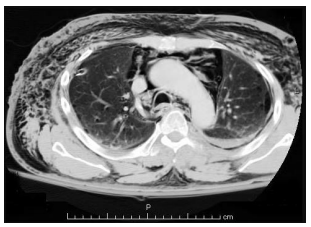

Homem de 18 anos, vítima de colisão moto x

auto há 2 horas, refere apenas muita dor

torácica para respirar, estando estável

hemodinamicamente. Exame físico

direcionado: enfisema de tecido celular

subcutâneo principalmente em região

anterior e lateral do tórax, expansibilidade

simétrica bilateralmente, murmúrio vesicular

presente bilateralmente, sem alteração à

percussão. A TC de tórax é apresentada a

seguir:

Assinale a alternativa correta em relação ao diagnóstico e a conduta adequada nesse caso.

Assinale a alternativa correta em relação ao diagnóstico e a conduta adequada nesse caso.